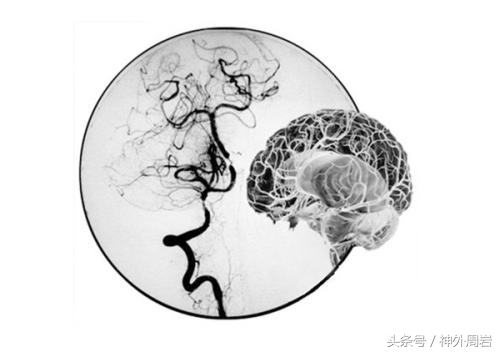

烟雾病是指由原发性颈内动脉末端狭窄、闭塞及脑底出现异常血管扩张网所致的出血性或缺血性疾病。因脑底异常血管网在脑血管造影像上似“烟雾状”或“朦胧状”,故而称之为“烟雾病”。

脑血管造影(又称为DSA)是临床确诊本病的主要手段。